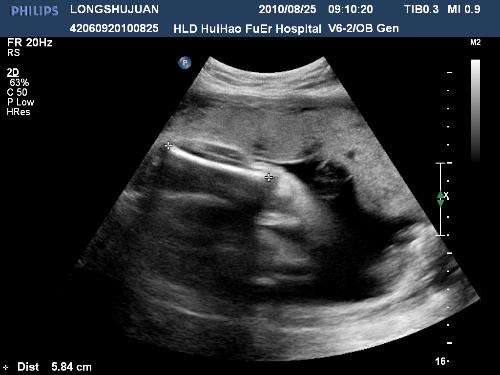

42天时去做第一次b超,就发现了有一点不对的地方,就是孕囊在左宫角那里,也许很多人,还不太了解,就是还没有到最里面,宝宝就在那里扎根了,如果乐观长长就进去了,如果不乐观,医生说就证明自己怀孕过。当然医生也不能说的那么绝对,就说明天再来一次,有专家来,再给看看。谁知这一来二去做了4次b超,让本来担心的小小,越来越担心了,心情也不再好了,这几天就哭了好几回,医生说先回家视察,只要不出血,就没有什么问题,再大一点再来视察,最主要的就是心情了。